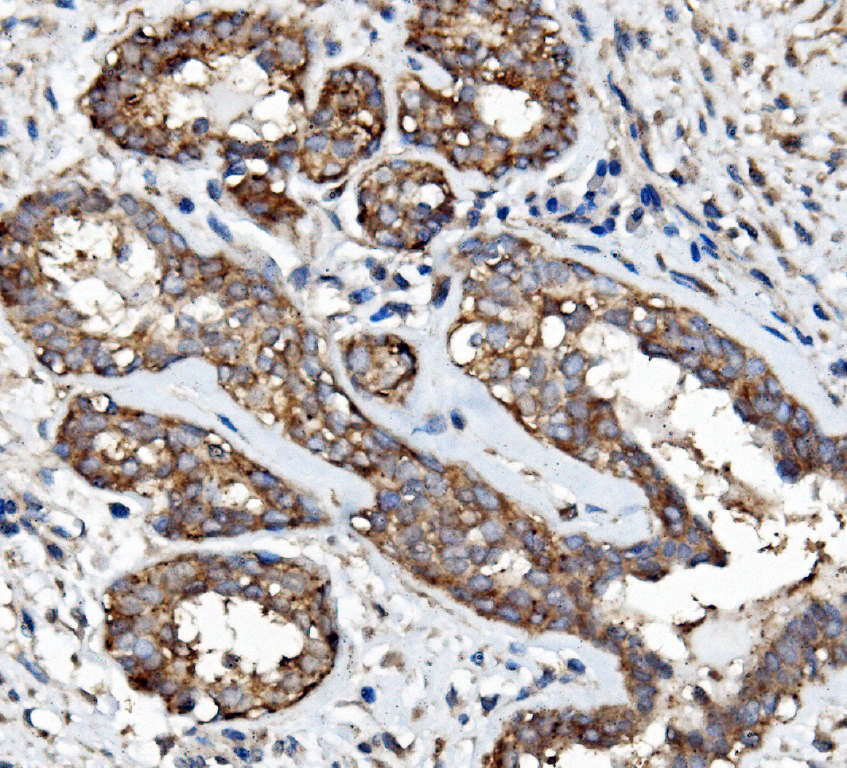

IHC analysis of EGFR using anti-EGFR antibody (A00023-4).

EGFR was detected in a paraffin-embedded section of human mammary cancer tissue. Biotinylated goat anti-rabbit IgG was used as secondary antibody. The tissue section was incubated with rabbit anti-EGFR Antibody (A00023-4) at a dilution of 1:200 and developed using Strepavidin-Biotin-Complex (SABC) (Catalog # SA1022) with DAB (Catalog # AR1027) as the chromogen.